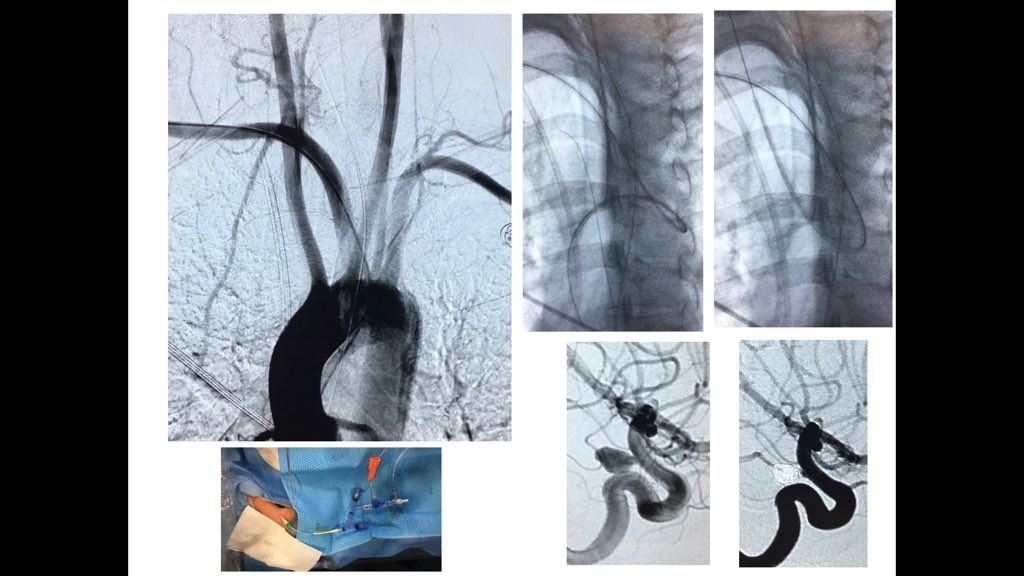

37yo female with SAH Fisher 4.right pcom aneurysm. #RadialFirst #radialforneuro difficulties to get in right carotid>aortography: easy when anatomic variant is understood. Do you see it? Oscar Chirife Sonia Aixut Lorenzo Hospital Universitari Bellvitge | HUB